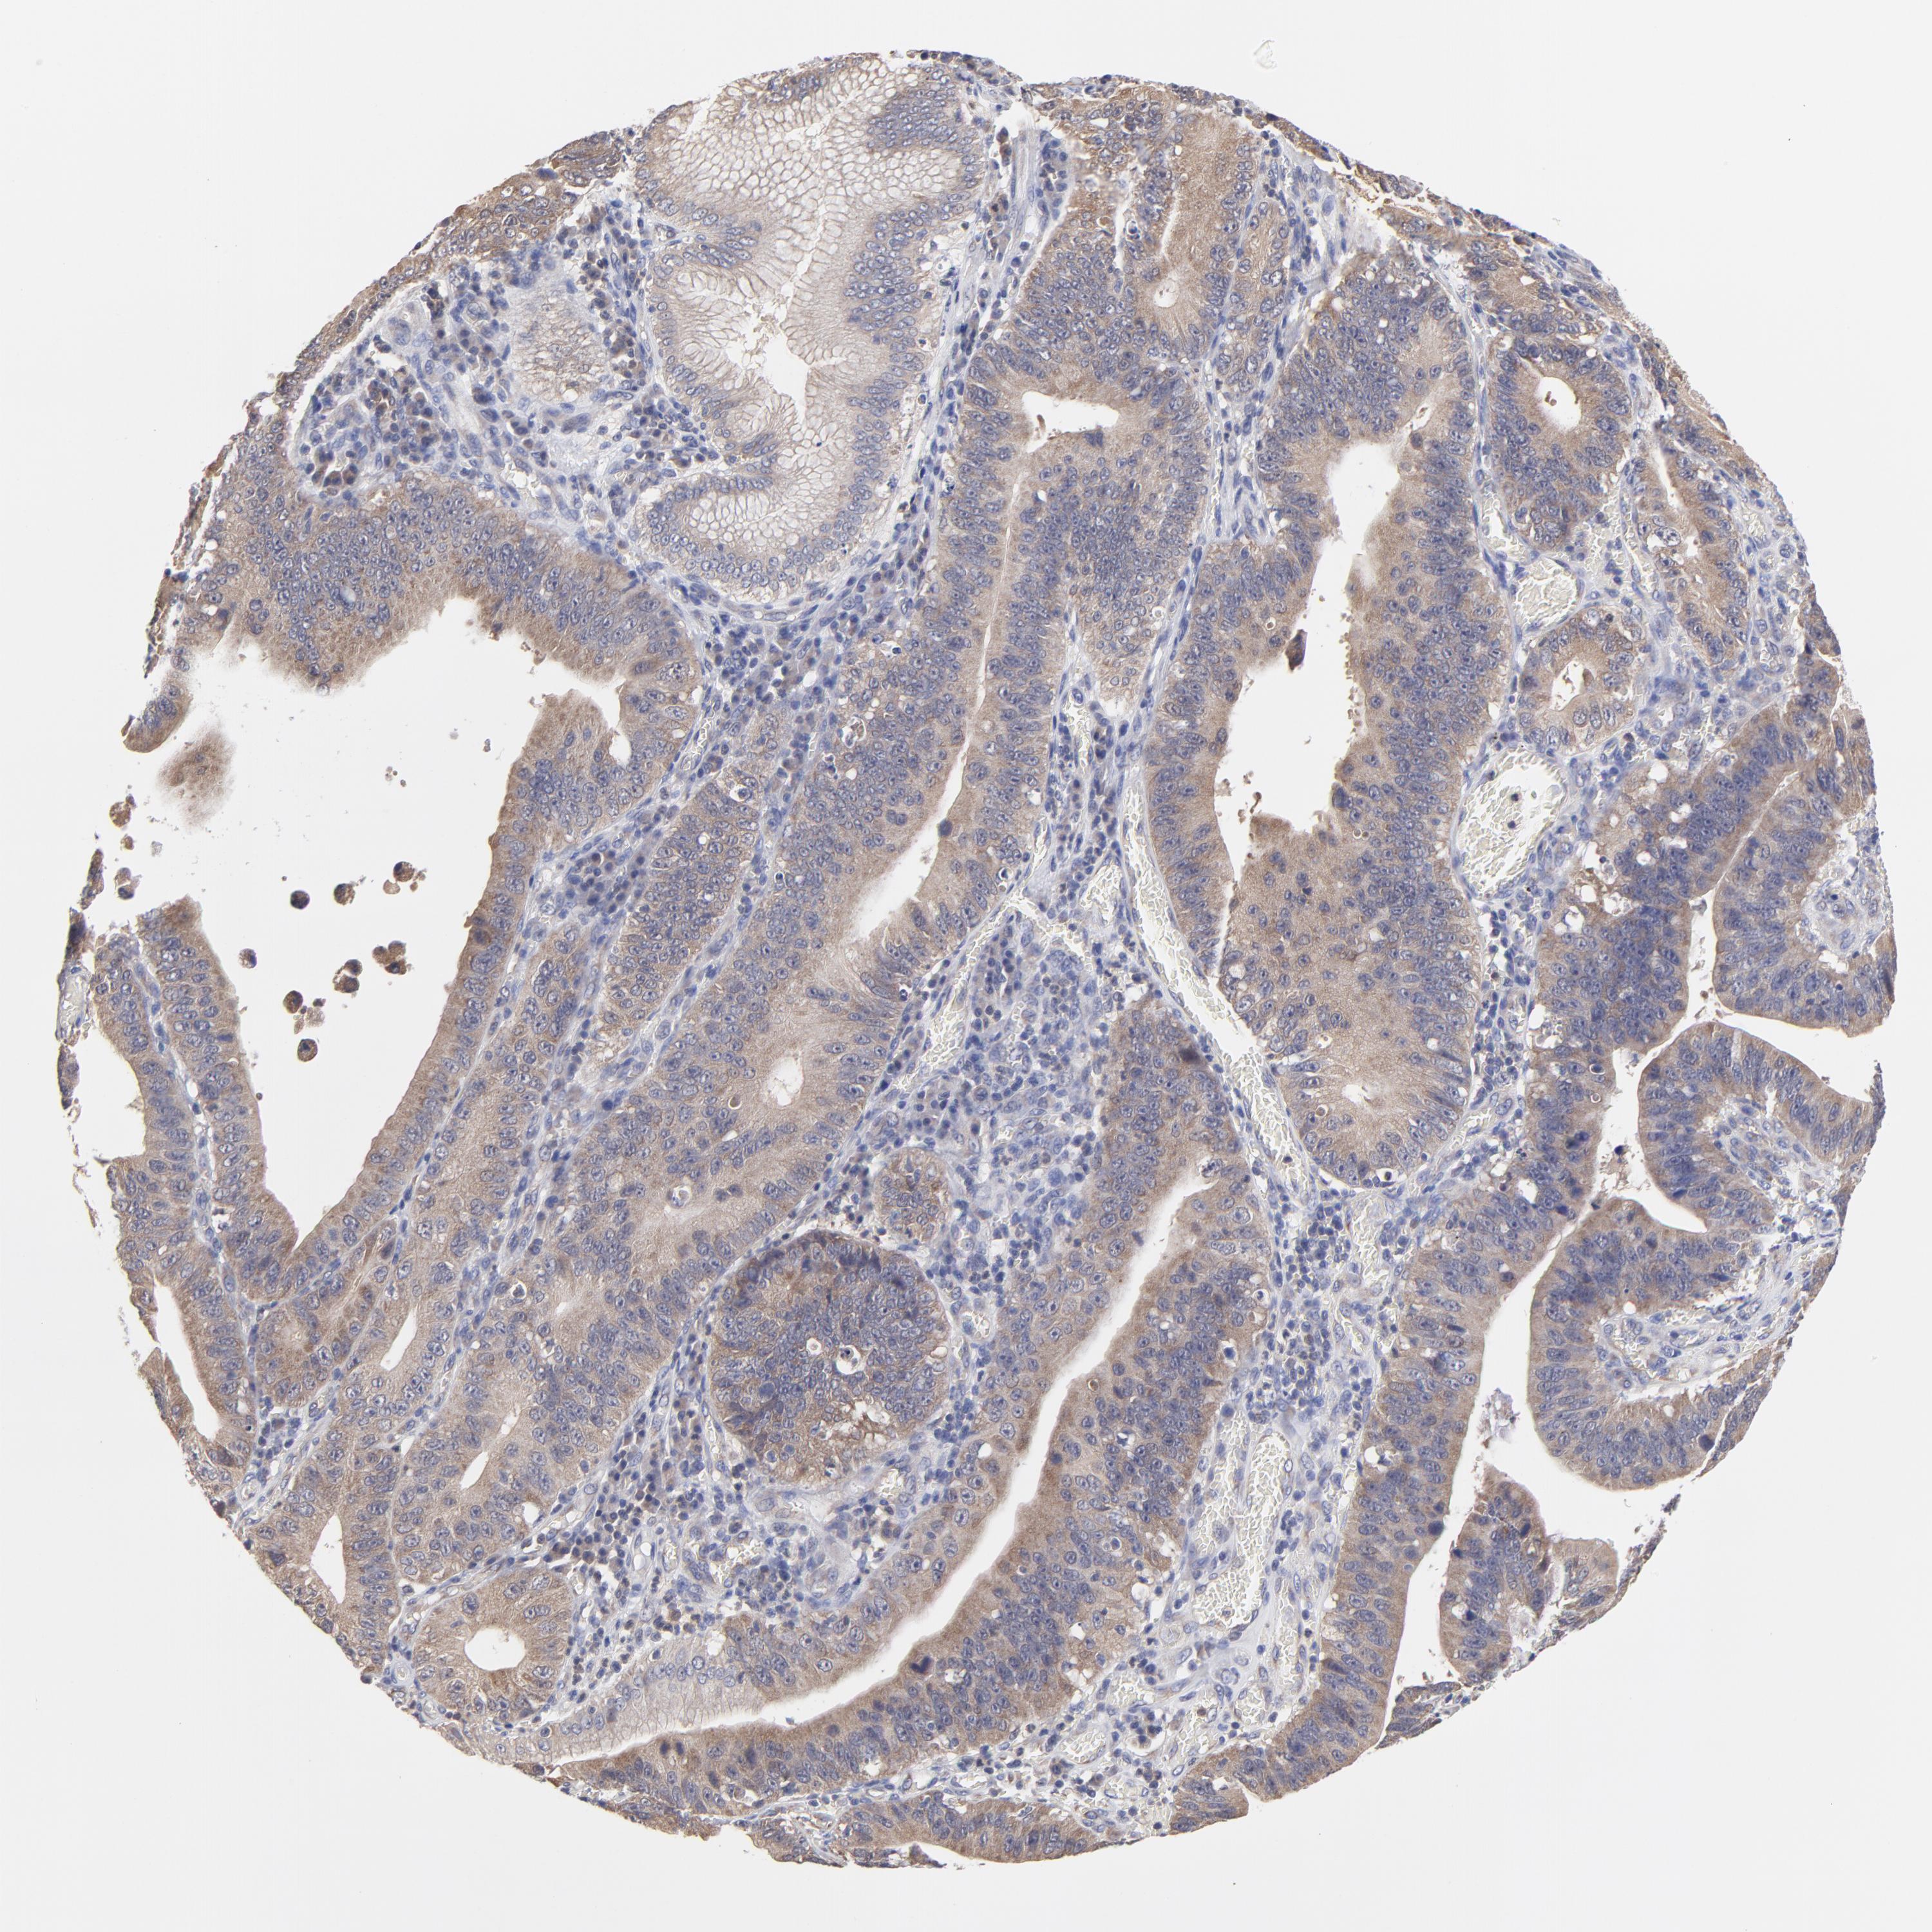

STOMACH CANCER - Protein expressioni

A mouse-over function shows sample information and annotation data. Click on an image to view it in a full screen mode. Samples can be filtered based on level of antibody staining by selecting one or several of the following categories: high, medium, low and not detected. The assay and annotation is described here.

Note that samples used for immunohistochemistry by the Human Protein Atlas do not correspond to samples in the TCGA dataset.

Antibody stainingi

Antibody staining in the annotated cell types in the current human tissue is reported as not detected, low, medium, or high, based on conventional immunohistochemistry profiling in selected tissues. This score is based on the combination of the staining intensity and fraction of stained cells.

Each image is clickable and will lead to virtual microscopy that enables deeper exploration of all samples and also displays staining intensity scores, fraction scores and subcellular localization as well as patient and tissue information for each sample.

Antibody HPA003239

Staining

High

Medium

Low

Not detected

Intensity

Strong

Moderate

Weak

Negative

Quantity

>75%

75%-25%

<25%

None

Location

Nuclear

Cytoplasmic/membranous

Cytoplasmic/membranous,nuclear

Adenocarcinoma, NOS

Adenocarcinoma, High grade